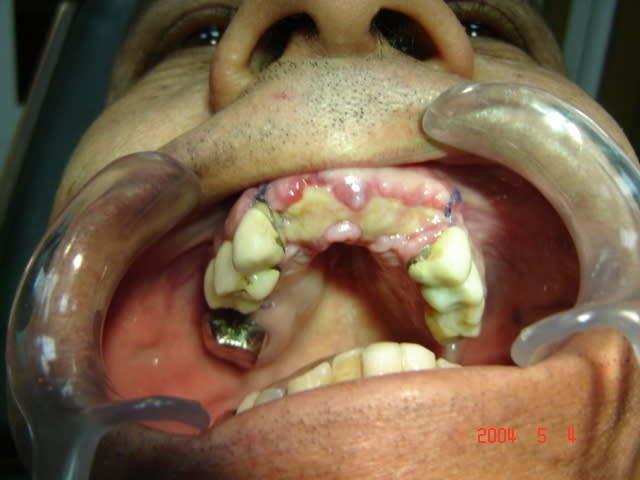

Comme promis , photos du cas a 22 jours post op.

qu'en pensez-vous

ksousou6

12/01/2006 à 13h56

et la troisieme .